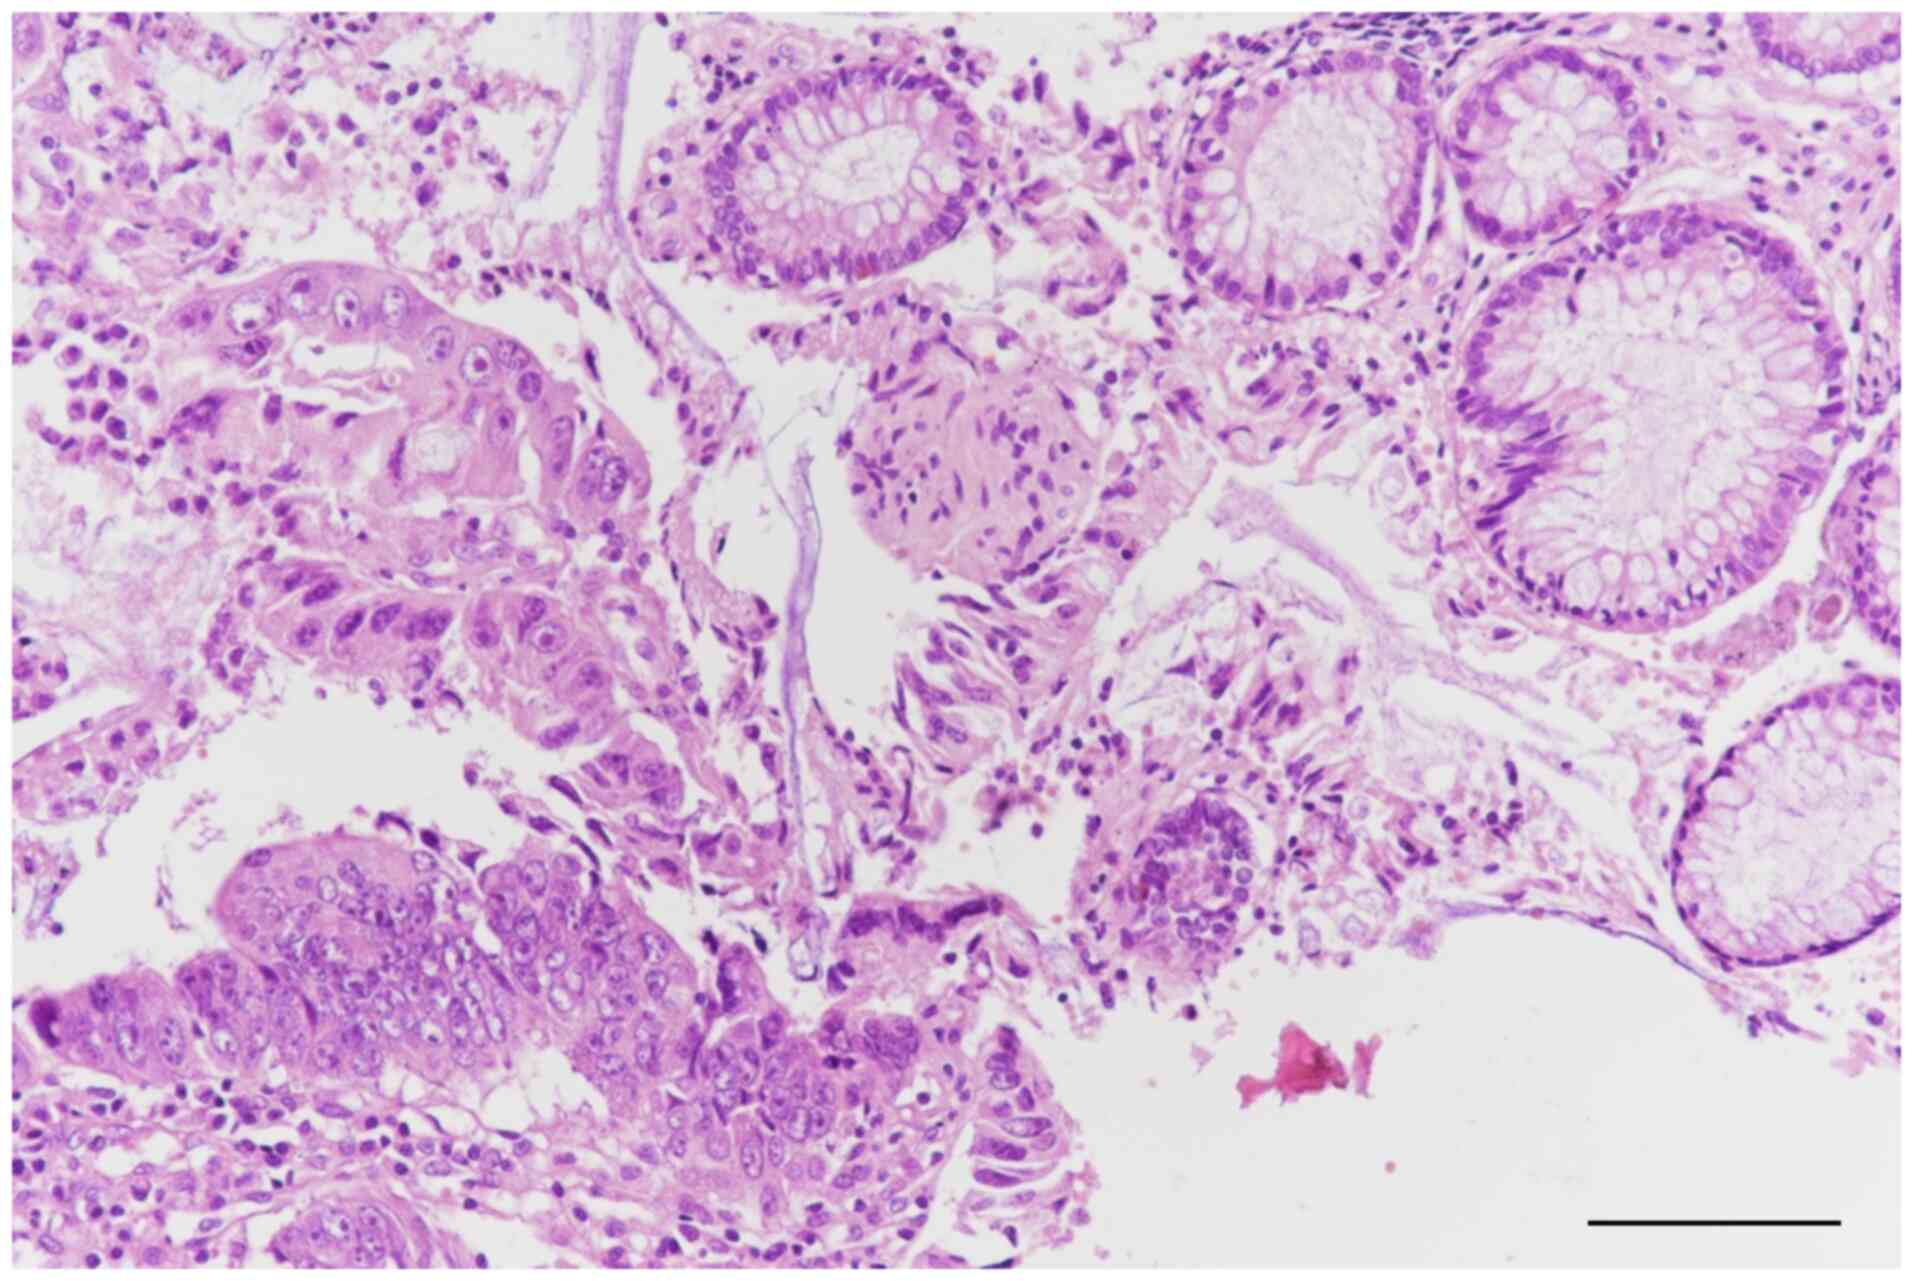

A superior digestive endoscopy did not reveal notable abnormalities. However, an inferior digestive endoscopy revealed a pedunculated polyp, which was biopsied for further examination (Fig. 2). The sample was first fixed in 10% neutral buffered formaldehyde, at room temperature for 24-48 h. Following fixation, the sample was embedded in paraffin and serial sections were cut at a thickness of 4 µm. The sections were stained with hematoxylin at room temperature for 5 min, followed by eosin for 2 min. The stained sections were examined under a light microscope at varying magnifications, in this case 20 and 40x. Histopathological examination revealed an adenomatous polyp with areas of moderately differentiated adenocarcinoma that did not involve the muscularis mucosae layer (Fig. 3, Fig. 4 and Fig. 5).

Figure 3

Histopathological examination revealed an adenomatous polyp with areas of moderately differentiated adenocarcinoma that did not involve the muscularis mucosae layer. Scale bar, 100 µm.

Figure 4

Moderately differentiated adenocarcinoma. Scale bar, 100 µm. Moderately differentiated adenocarcinoma was identified by histopathological examination of the biopsy samples.

An inferior digestive endoscopy revealed a pedunculated polyp in the descending colon and an endoscopic polypectomy was subsequently performed. Histopathological examination confirmed the presence of a malignant polyp with areas of moderately differentiated adenocarcinoma infiltrating the submucosal layer, as well as regions classified as carcinoma in situ not extending beyond the muscularis mucosae layer (Fig. 3).